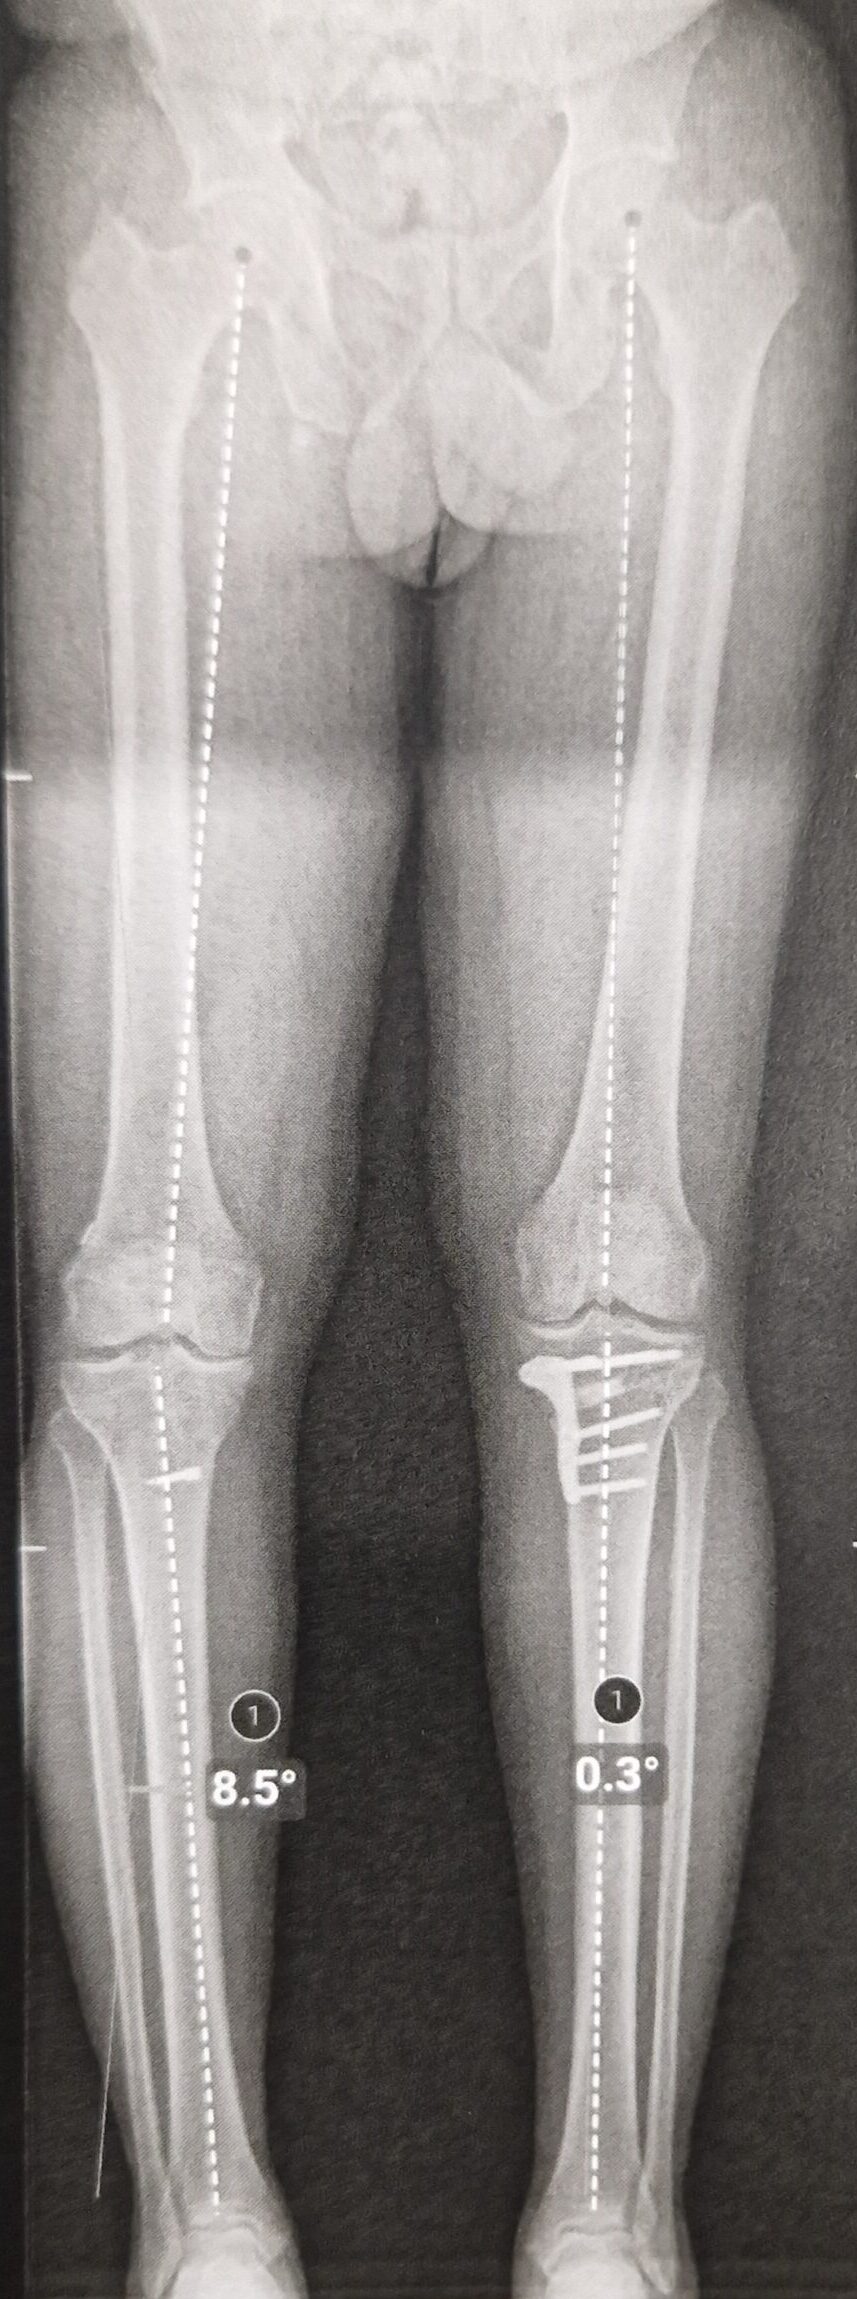

L’axe mécanique du membre est mesuré pour déterminer l’angle exact de correction nécessaire.